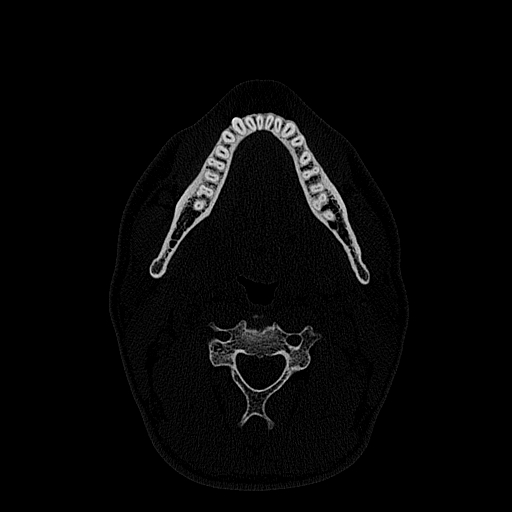

Мультиспиральная дентальная компьютерная томография (МДКТ или, как ее еще называют, КТ зубов) – это современный высокоточный метод лучевой диагностики, с помощью которого получают объемные цифровые изображения всей зубочелюстной системы. В основе метода лежит применение рентгеновского излучения и последующая цифровая обработка полученных данных специальными компьютерными программами.

Мультиспиральный томограф выполняет послойное сканирование области верхней и нижней челюстей с помощью рентгеновских лучей, а затем, используя компьютерную обработку данных, создает 3D-модели исследуемой зоны. Современные модели томографов проводят круговое сканирование по спирали, делая срезовые снимки на расстоянии 0,5 мм друг от друга. Затем на основе этих данных реконструируются детальные изображения челюстно-лицевой области в трехмерном формате.

В отличие от конусно-лучевой компьютерной томографии (КЛКТ), которая также в последнее время применяется в стоматологии, МДКТ помогает лучше визуализировать костные структуры на фоне артефактов от имплантов и протезов, выполнить сканирование быстрее, без двигательных артефактов, в любом объеме под запрос вашего ортодонта.

Исследование занимает всего пару минут. Данные, полученные при сканировании, проходят цифровую обработку и выводятся на монитор компьютера в виде 3D-изображений. Врач-рентгенолог внимательно анализирует данные и выдает заключение.